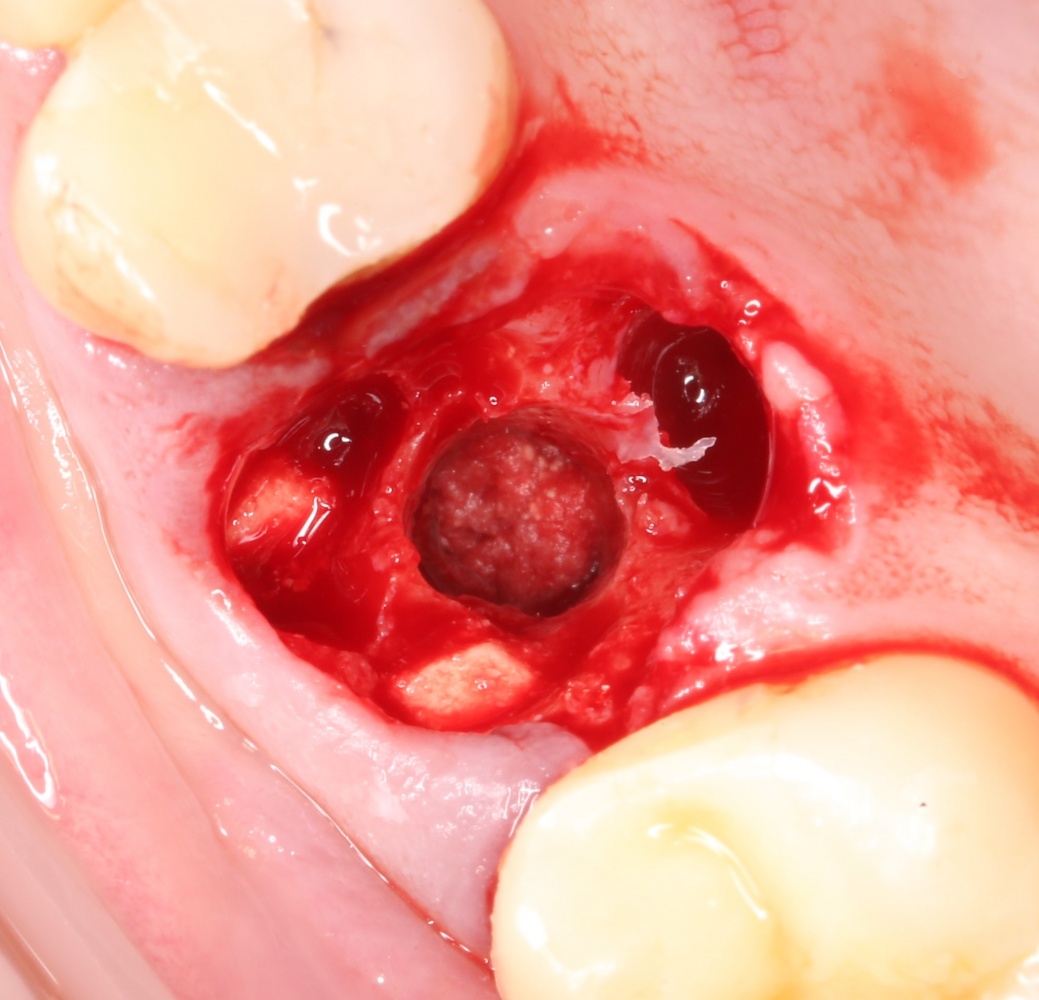

В ходе проведения операции синуслифтинга, у нас образовалась небольшая перфорация шнайдеровой мембраны:

Мы начинаем с того, что выводим ее в центр апертуры, попутно мобилизуем края. В результате, она несколько уменьшилась в размерах:

В данном случае я использовал Geistlich Mucograft Seal 8mm. Биоматериал в данном форм-факторе стоит дешевле, чем барьерная мембрана, а его диаметр позволяет легко перекрыть образовавшийся дефект слизистой:

Перед позиционированием Mucograft лучше намочить. Он станет более эластичным (без потери прочности) и мягким:

После чего, он легко приклеивается и перекрывает дефект:

Нам лишь остается заполнить образовавшееся субантральное пространство графтом (Bio-Oss) и закончить операцию синуслифтинга и остеопластики так, как мы планировали: